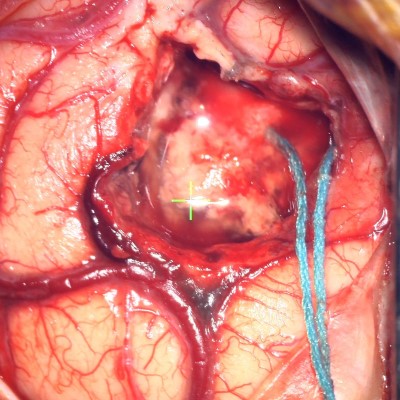

Intraoperative video obtained through the surgical microscope. The tumor has been debulked and dissected free from the surrounding brain. Video shows the final removal of the tumor.